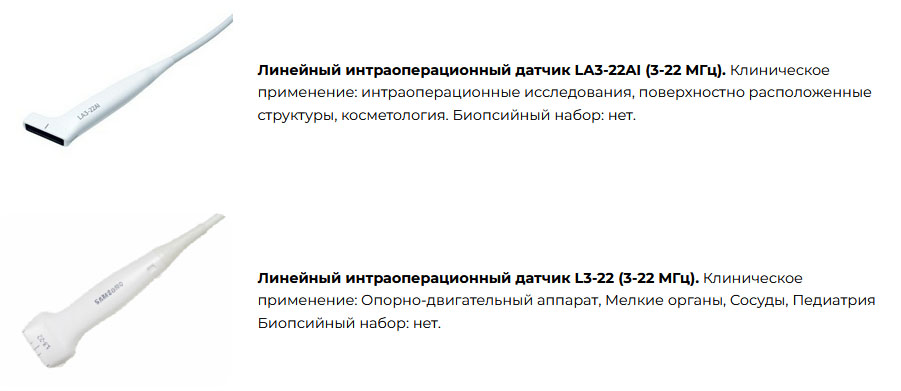

Датчики

Линейные датчики